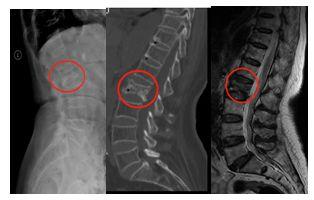

前不久,76岁的谭奶奶突然腰背部剧痛,谭奶奶在床上躺了几天,疼痛没有好转,甚至越来越痛,连翻身都很困难!于是,谭奶奶在家人的陪同下来到广州中医药大学第一附属医院脊柱骨科张顺聪教授门诊就诊,经脊柱的体格检查和拍片发现原来是腰椎椎体发生了压缩性骨折,谭奶奶十分迷惑,没受过伤的,怎么莫名其妙就骨折了?

老年人突然出现的腰痛,首先要考虑的是骨质疏松性脊柱骨折。顾名思义,这种骨折大多是骨质疏松惹得祸! 随着年龄增大,各种营养物质的吸收减少了,特别是钙质的吸收减少,骨头变得“脆弱”起来了。随着人口老龄化问题日趋严重,骨质疏松症已成为我国面临的重要公共健康问题。

骨质疏松性骨折指受到轻微创伤或日常活动中即发生的骨折,是骨质疏松症的严重后果。骨质疏松性骨折的常见部位是脊柱椎体、髋部、前臂远端、肱骨近端和骨盆等,其中最常见的是椎体骨折。有资料记载,50岁以上女性椎体骨折患病率约为15%,50岁以后椎体骨折的患病率随增龄而渐增,80岁以上女性椎体骨折患病率可高达36.6%。这相当于每10个人中就有3-4个人发生骨质疏松行椎体骨折!

骨质疏松性脊柱骨折往往外伤较轻,或无明显外伤史,有时打喷嚏、咳嗽、弯腰甚至用力排便等都可以导致骨折。同时,由于部分病人初期腰背痛症状不明显,对骨折的重视不够,由于不当的治疗方式,容易造成严重后果。

需要注意的是,老人家突然腰背痛除了考虑骨质疏松性椎体压缩骨折以外,还有可能是脊柱肿瘤、结核、感染以及泌尿系统、消化系统等其他内科疾病。因此,老年人突然出现腰痛,应当及时到医院就诊,以免贻误病情。